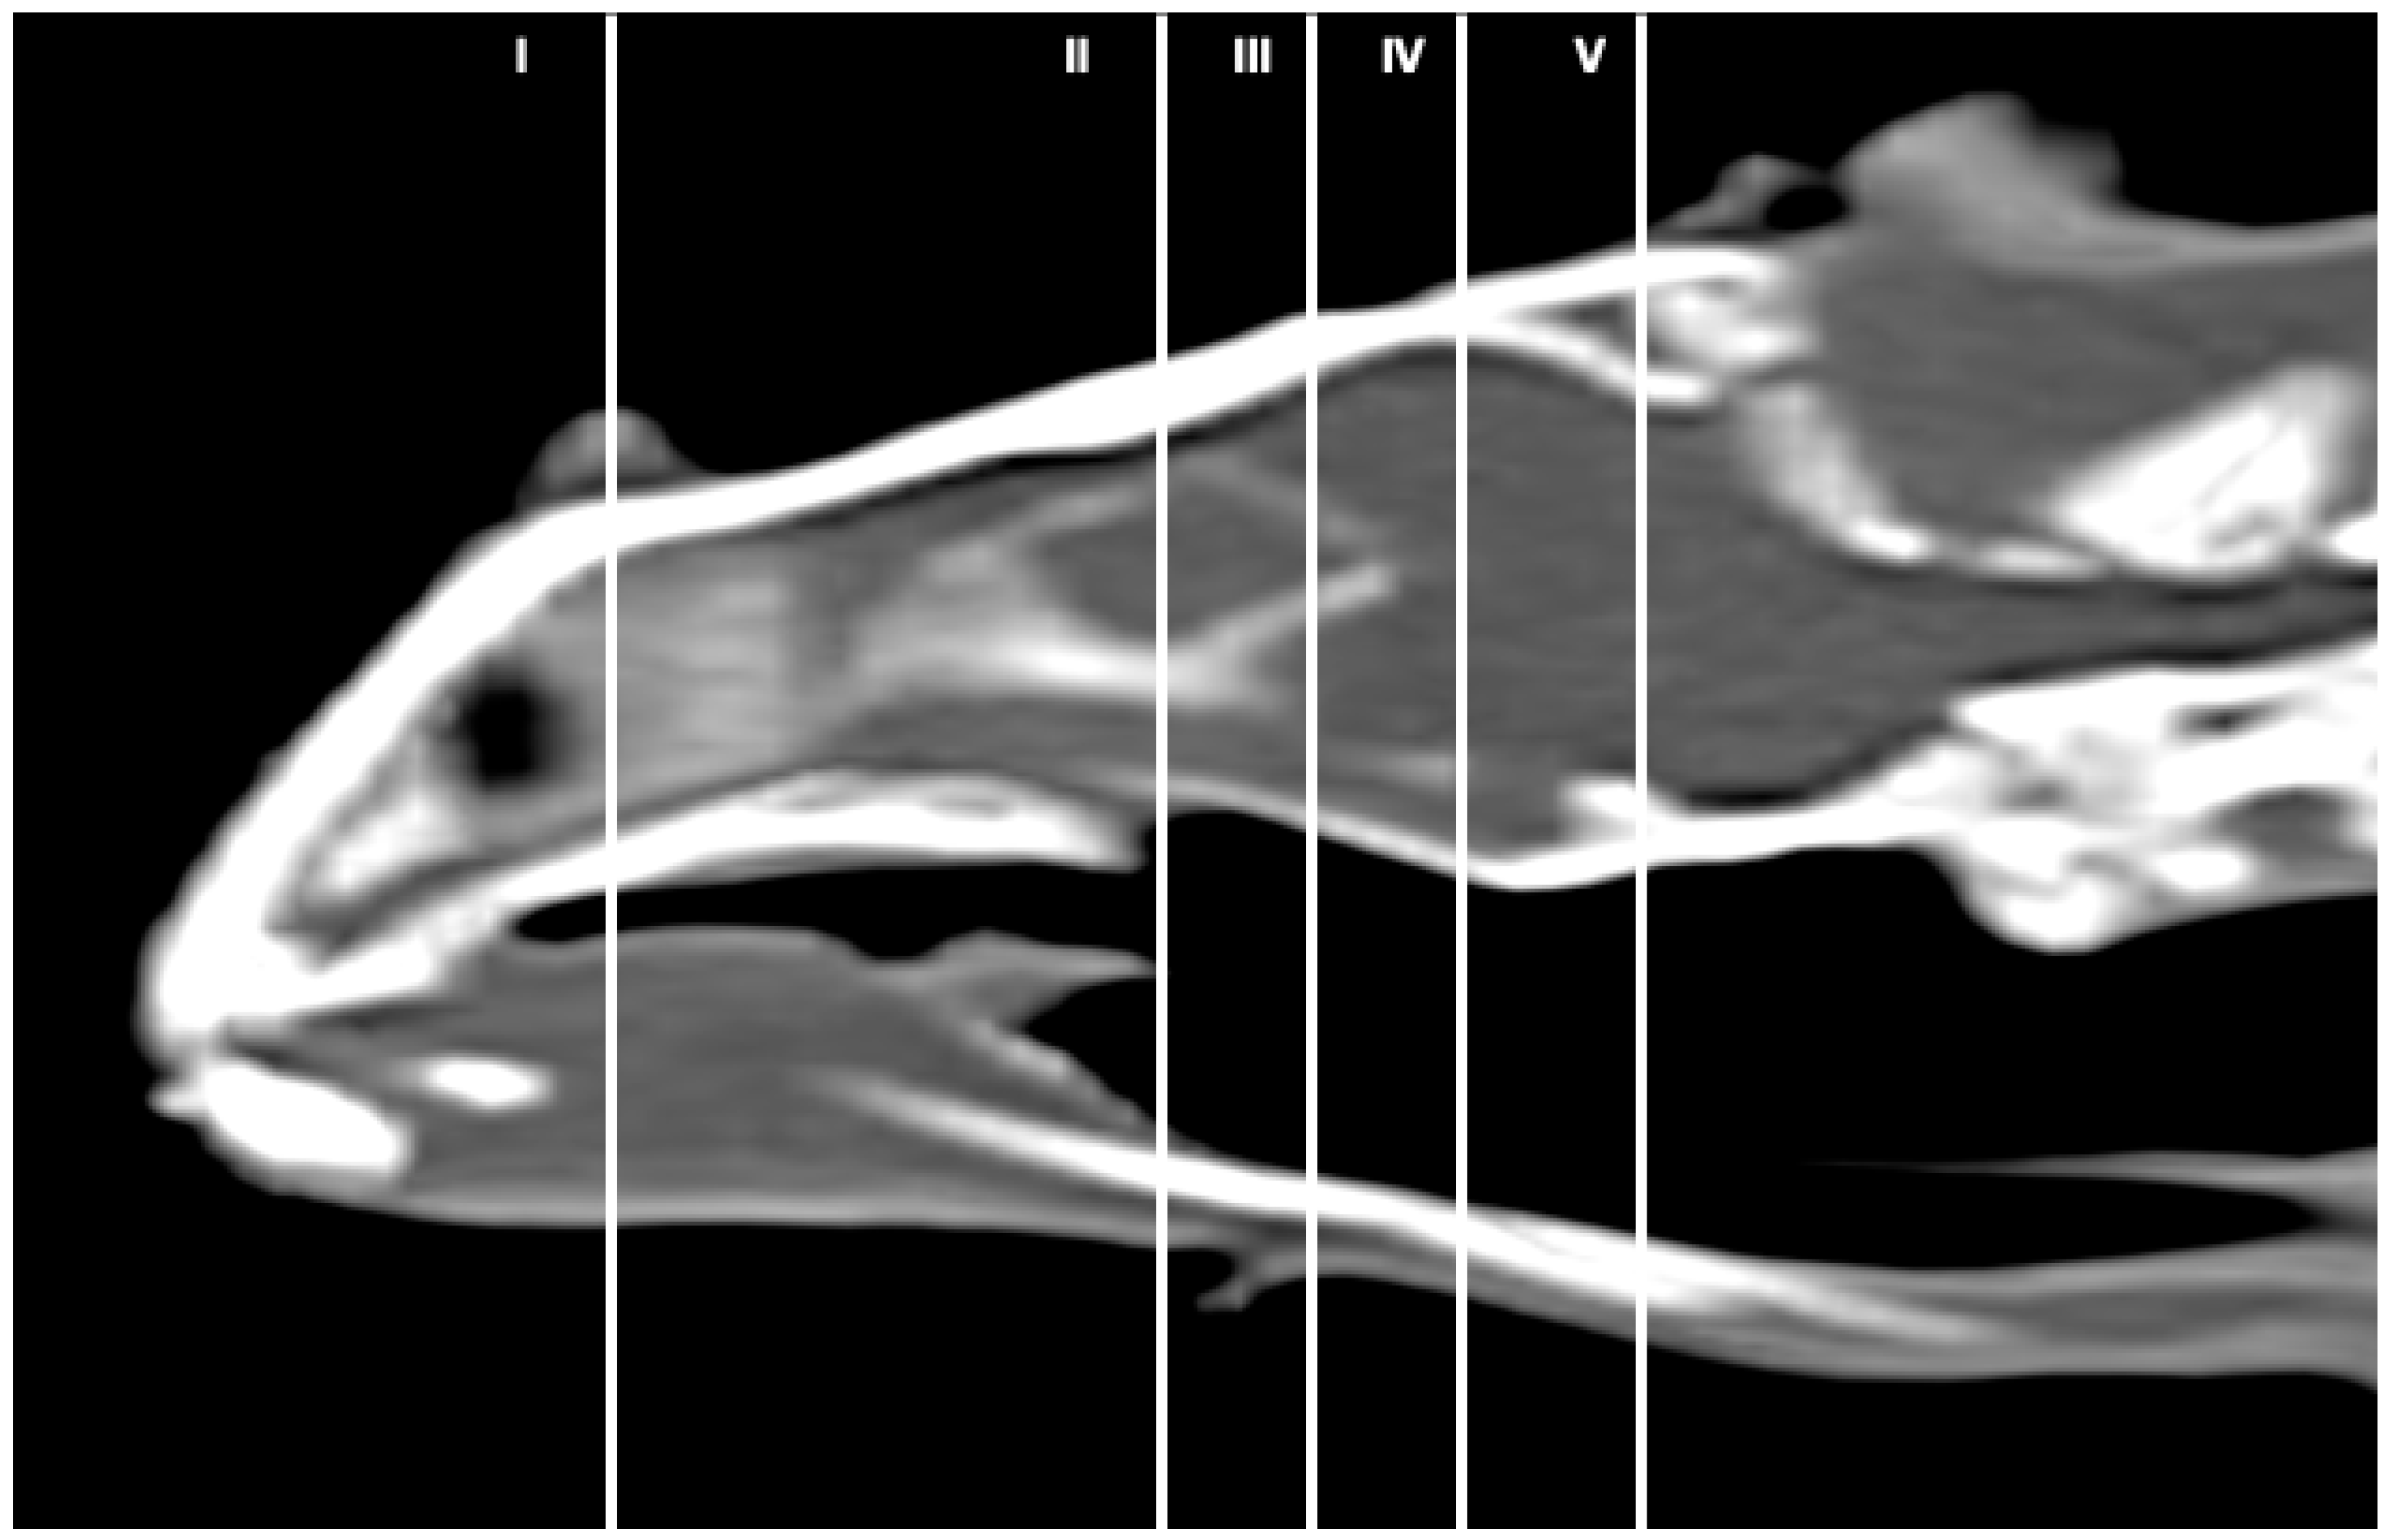

3.1. Anatomical Sections

3.2. Computed Tomography (CT)

3.3. Magnetic Resonance Imaging (MRI)